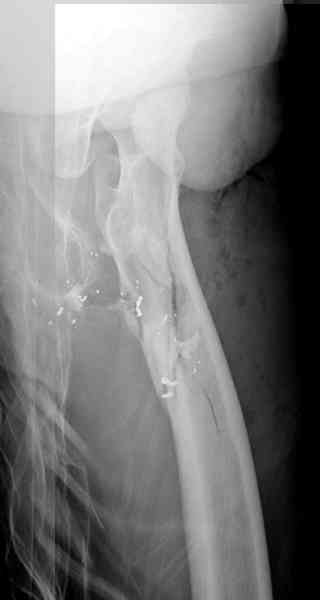

Несмотря на высокоэнергетический характер ранения, пуля не попала непосредственно в кость, а прошла рядом. Таким образом, для бедренной кости это ранение нельзя назватьв полном смысле этого слова высокоэнергетическим. К сожалению, не видно выходное отверстие. В любом случае, при таком переломе интрамедуллярный остеосинтез вполне показан. Кроме того, если пациент попал к Вам в первые часы после ранения, рана не должна рассматриваться как инфицированная. В качестве примера возможности даже более травматичной операции при таком характере перелома привожу следующий случай.

Пациент оперирован на 5-е сутки (переведен из другого лечебного учреждения)после сквозного пулевого ранения плеча и грудной клетки (непроникающее ранение той же пулей). Выполнен минимально инвазивный остеосинтез блокируемой метадиафизарной пластиной, повторная хирургическая обработка ран плеча. Заживление всех ран первичное, сращение наступило в обычные сроки.